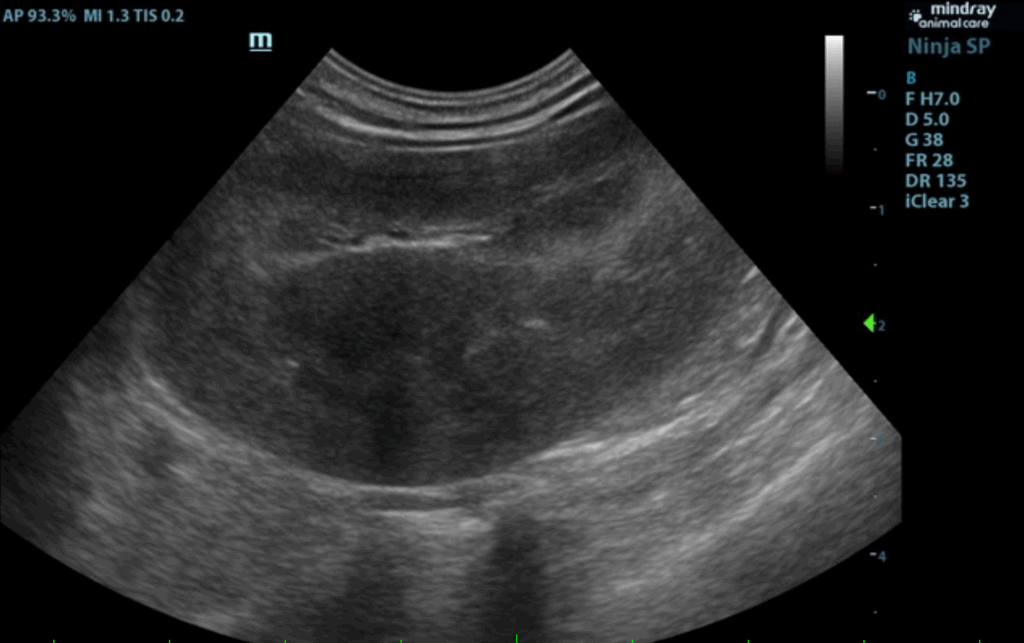

The spleen in this patient was mildly enlarged with uniform parenchyma and was folded upon itself caudally. This is a positional variant and is not pathological. There was no evidence of significant disease.

Liver:

The liver was mildly subnormal in size. The hepatic parenchyma was uniform, yet hypovascular owing to the extrahepatic shunting. The extrahepatic shunt decoursed ventral caudally and then dorsally. It appeared to bypass the vena cava and aorta. It likely entered into the azygos, however, the termination

could not be found given the lack of acoustic window. The hepatic width was approximately 2.0 cm in short axis. The portal vein was subnormal in size and measured 0.34 cm after the gastroduodenal vein junction. An extrahepatic vessel was present just caudal to the pylorus and measured 1.05 cm. This is

consistent with gastric shunt. The aorta and vena cava both measured approximately 0.65 cm. The gallbladder and common bile were unremarkable.